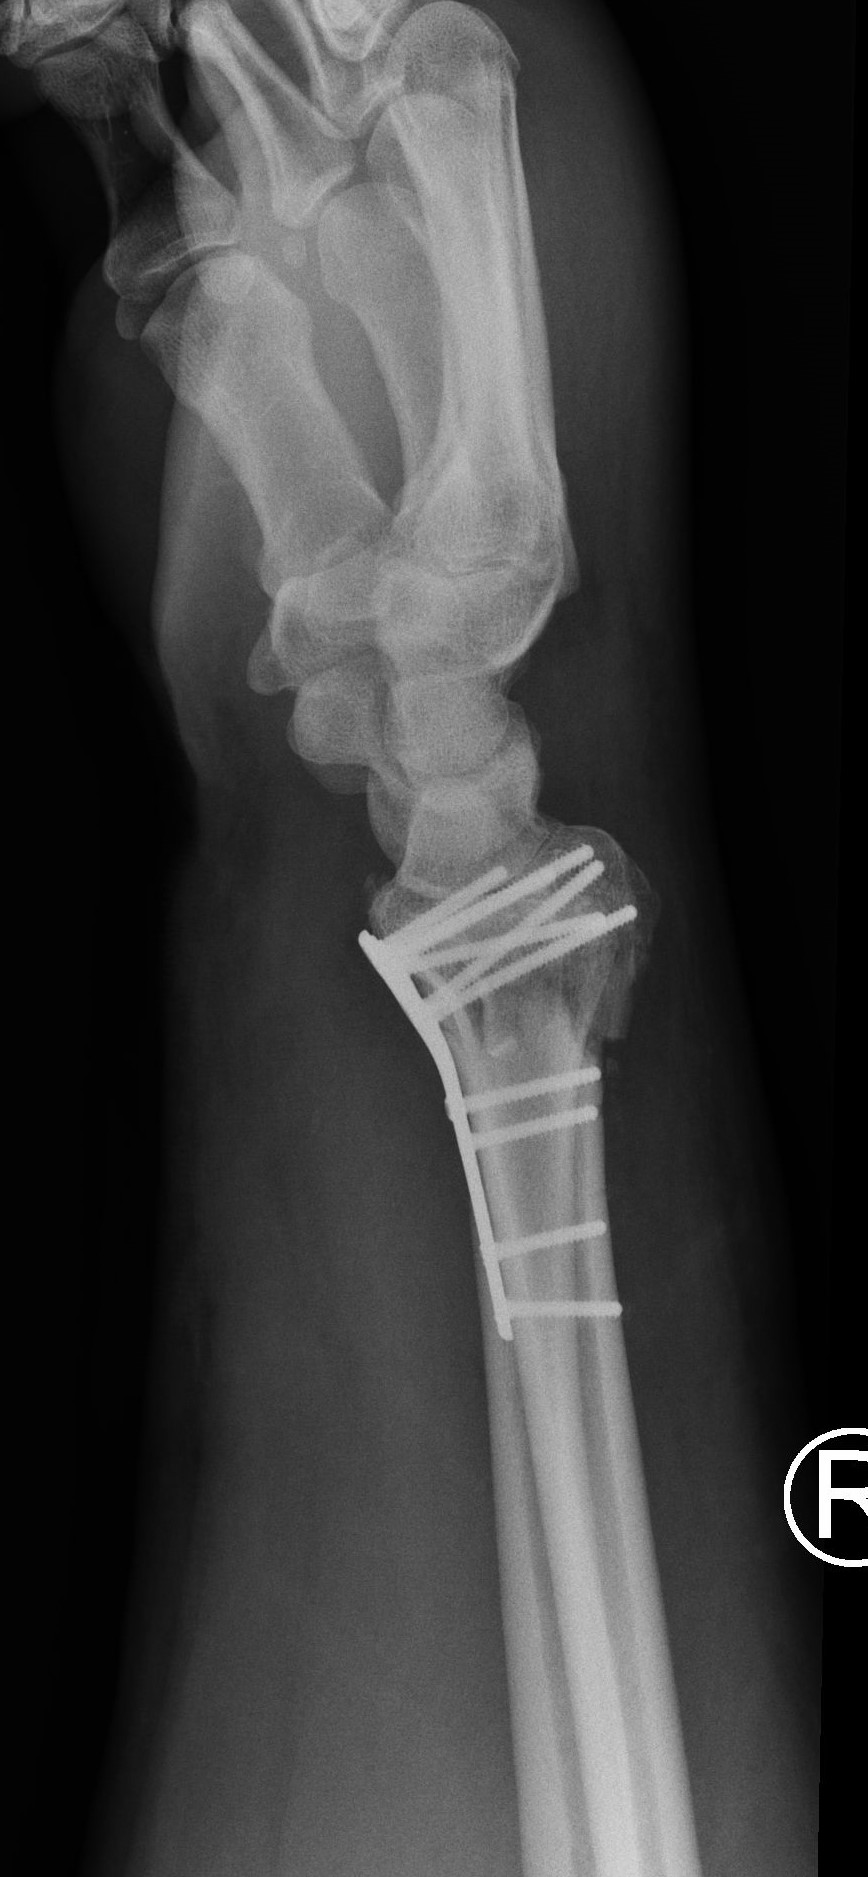

Interposition of the index flexor digitorum superficialis tendon beneath a fragment of the distal radius fracture: a case report

High-energy distal radius fractures are characterized by significant displacement of bone fragments, articular surface damage, and ligamentous injury. Tendon interposition between bone fragments occurs very rarely. In this report, we present a case of a complex distal radius fracture in which intraoperative findings revealed interposition of the flexor digitorum superficialis tendon of the index finger beneath one of the fracture fragments. The exceptional rarity of this situation prompted the authors to report this case.